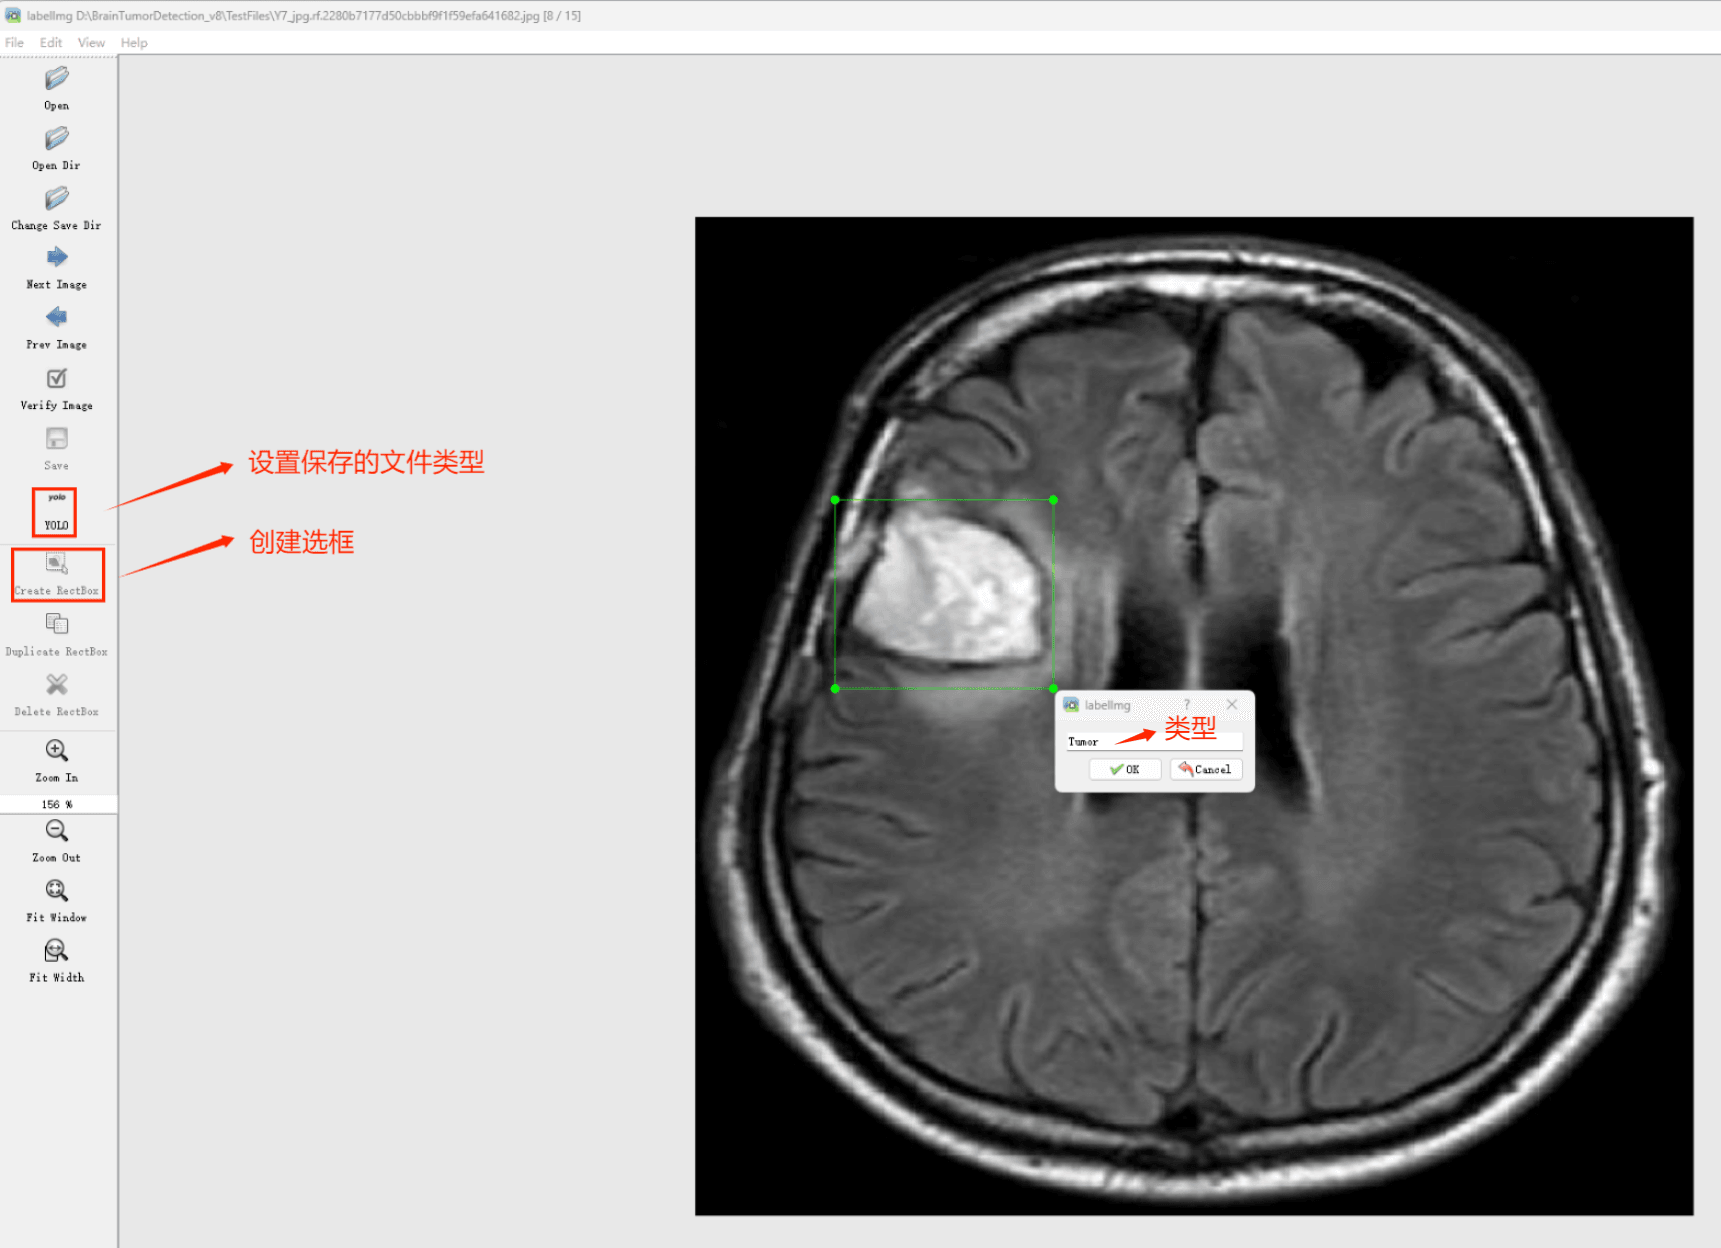

(1)labelimg:开源的图像标注工具,标签可用于分类和目标检测,它是用python写的,并使用Qt作为其图形界面,简单好用(虽然是英文版的)。其注释以 PASCAL VOC格式保存为XML文件,这是ImageNet使用的格式。此外,它还支持 COCO数据集格式。

初识labelimg

打开后,我们自己设置一下

在View中勾选Auto Save mode

接下来我们打开需要标注的图片文件夹

并设置标注文件保存的目录(上图中的Change Save Dir)

接下来就开始标注,画框,标记目标的label,然后d切换到下一张继续标注,不断重复重复。

(4)YOLO模式创建标签的样式

存放标签信息的文件的文件名为与图片名相同,内容由N行5列数据组成。

每一行代表标注的一个目标,通常包括五个数据,从左到右依次为:类别id、x_center、y_center、width、height。